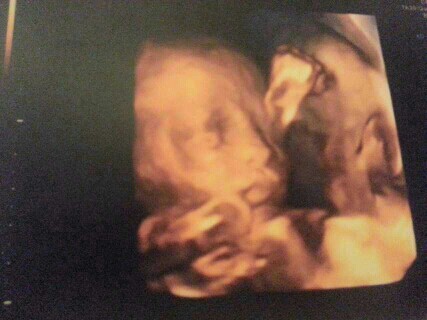

晒晒我的小公主:

这是照四维时候的照片,一切都很好,那时候医生就说宝宝很活跃很可爱!